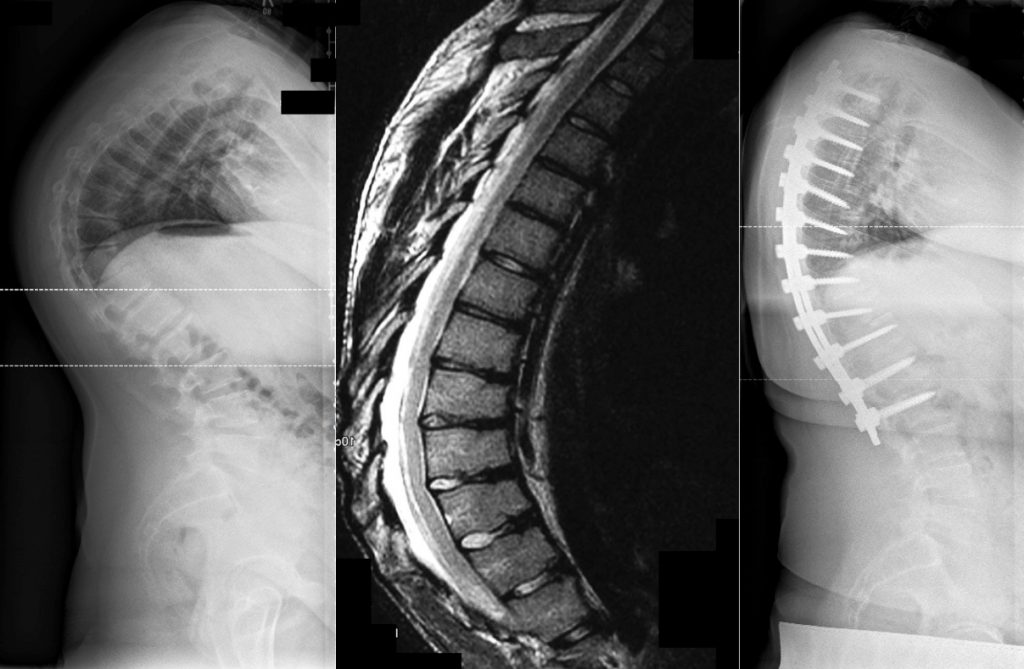

Post scheuermann syndrom. CT scan usually not needed;. In 1921, Danish radiologist Holger Werfel Scheuermann described the characteristic rigid kyphotic deformity that differed from the more flexible postural round back Today, the etiology remains. Adolescents with Scheuermann's disease are often asymptomatic (3,1) An estimated % of patients with Scheuermann's disease present with dull, aching, intermittent pain in the kyphotic curve, fatigue, and spinal tenderness or stiffness (3,1) Low back pain afflicts as many as 80% of patients with Scheuermann's disease (3).

Scheuermann's syndrome usually begins around 15 years of age and is selflimiting within about 2 years Hopefully at your age, the active disease process will have burnedout. Though people with Scheuermann’s disease are prohibited by a curve in their upper back from extensive twisting and bending, they can perform or modify some Pilates exercises to suit their abilities Pilates strengthens the core, which promotes upright posture, flexibility and range of motion. MRI controversial as to whether it is indicated prior to surgery to look for associated disc herniation, epidural cyst, spinal cord abnormalities, and spinal stenosis.

Scheuermann’s kyphosis is a developmental form of kyphosis, which means that it occurs in adolescents while their bodies are growing Normal vertebrae are rectangular in shape and are stacked on top of one another like building blocks, with a disc that acts as a soft cushion between each one. Was gibt es für alternativen ausser gym das mache ich schon regelmässig seit jahren , akkupunktur auch nicht sehr besonders hilfreich Bin 36 und vor 8 jahren nach langer odyssee wurde mir dann das post scheuermann syndrom diagnostiziert seit daher bin ich ständig in behandlung aber nichts hilft ist manchmal zum verzweifeln. Figure 1 A 13yearold boy with Scheuermann’s kyphosis Appearance of the patient in (A) standing and (B) forward bending positions Lateral radiograph of the thoracic spine shows kyphotic.